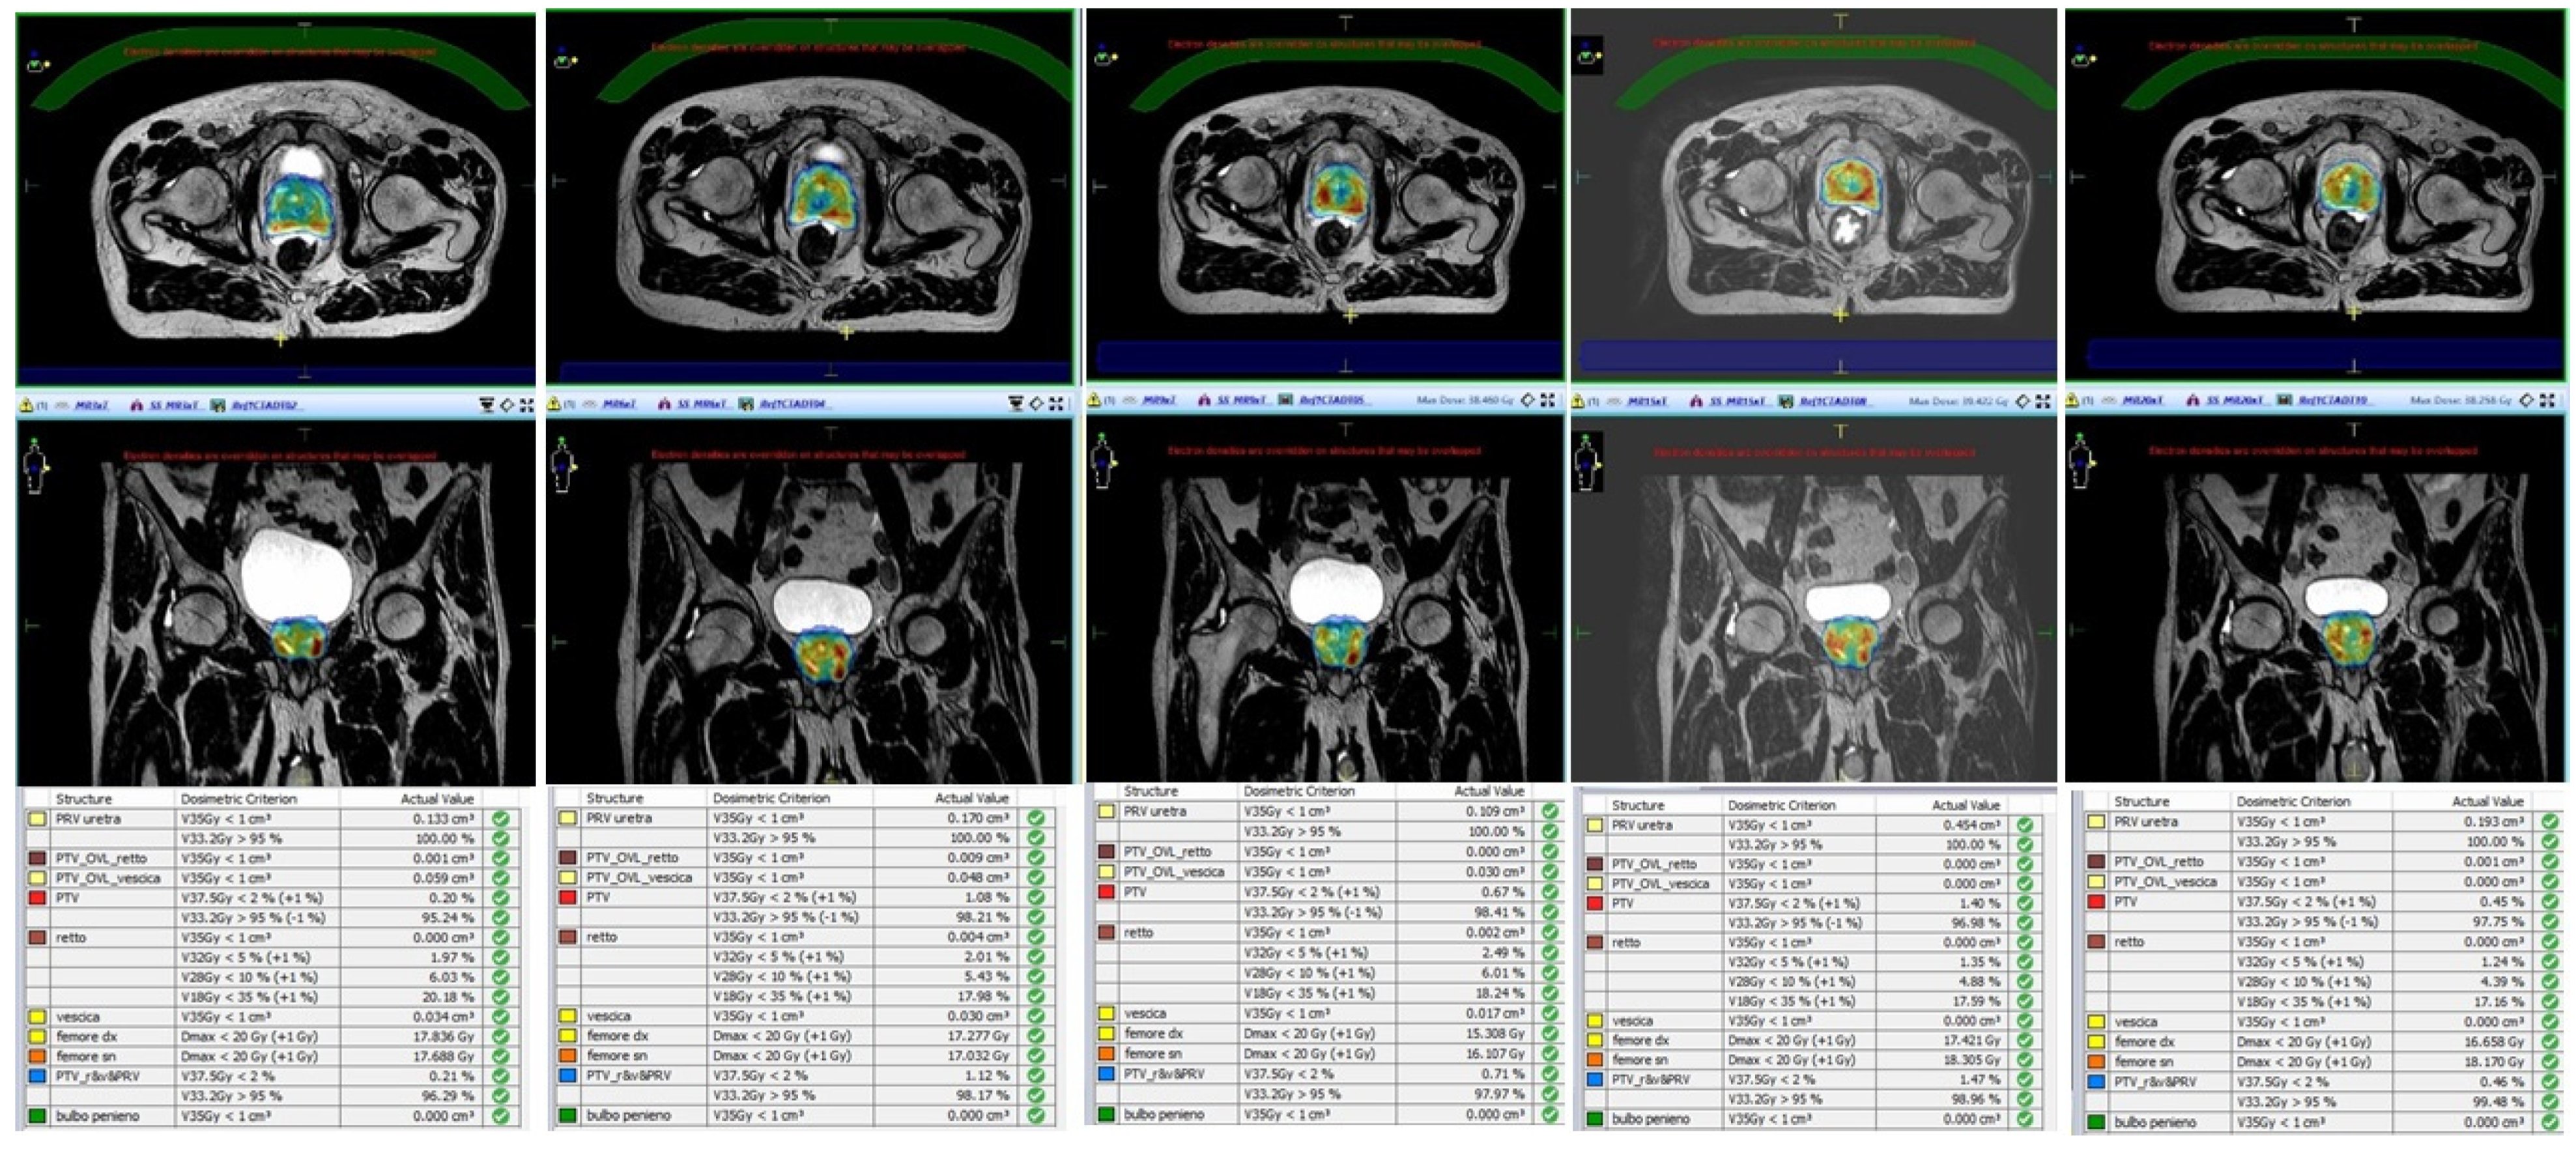

- Alongi, F.; Rigo, M.; Figlia, V.; Cuccia, F.; Giaj-Levra, N.; Nicosia, L.; Ricchetti, F.; Sicignano, G.; De Simone, A.; Naccarato, S.; et al. 1.5 T MR-guided and daily adapted SBRT for prostate cancer: Feasibility, preliminary clinical tolerability, quality of life and patient-reported outcomes during treatment. Radiat. Oncol. 2020, 15, 1–9. [Google Scholar] [CrossRef]

- Nicosia, L.; Sicignano, G.; Rigo, M.; Figlia, V.; Cuccia, F.; De Simone, A.; Giaj-Levra, N.; Mazzola, R.; Naccarato, S.; Ricchetti, F.; et al. Daily dosimetric variation between image-guided volumetric modulated arc radiotherapy and MR-guided daily adaptive radiotherapy for prostate cancer stereotactic body radiotherapy. Acta Oncol. 2021, 60, 215–221. [Google Scholar] [CrossRef] [PubMed]

- Ruggieri, R.; Rigo, M.; Naccarato, S.; Gurrera, D.; Figlia, V.; Mazzola, R.; Ricchetti, F.; Nicosia, L.; Giaj-Levra, N.; Cuccia, F.; et al. Adaptive SBRT by 1.5 T MR-linac for prostate cancer: On the accuracy of dose delivery in view of the prolonged session time. Phys. Med. 2020, 80, 34–41. [Google Scholar] [CrossRef] [PubMed]

- Dunlop, A.; Mitchell, A.; Tree, A.; Barnes, H.; Bower, L.; Chick, J.; Goodwin, E.; Herbert, T.; Lawes, R.; McNair, H.; et al. Daily adaptive radiotherapy for patients with prostate cancer using a high field MR-linac: Initial clinical experiences and assessment of delivered doses compared to a C-arm linac. Clin. Transl. Radiat. Oncol. 2020, 23, 35–42. [Google Scholar] [CrossRef]

- Mannerberg, A.; Persson, E.; Jonsson, J.; Gustafsson, C.J.; Gunnlaugsson, A.; Olsson, L.E.; Ceberg, S. Dosimetric effects of adaptive prostate cancer radiotherapy in an MR-linac workflow. Radiat. Oncol. 2020, 15, 1–9. [Google Scholar] [CrossRef]